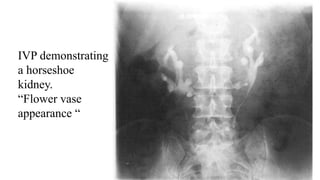

IVP demonstrating

a horseshoe

kidney.

“Flower vase

appearance “